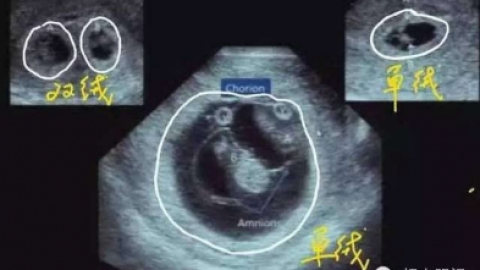

多胎妊娠PPT课件_语文_小学教育_教育专区

或以上胎儿。的胎儿数),以双胎最常见。的3-5倍,...